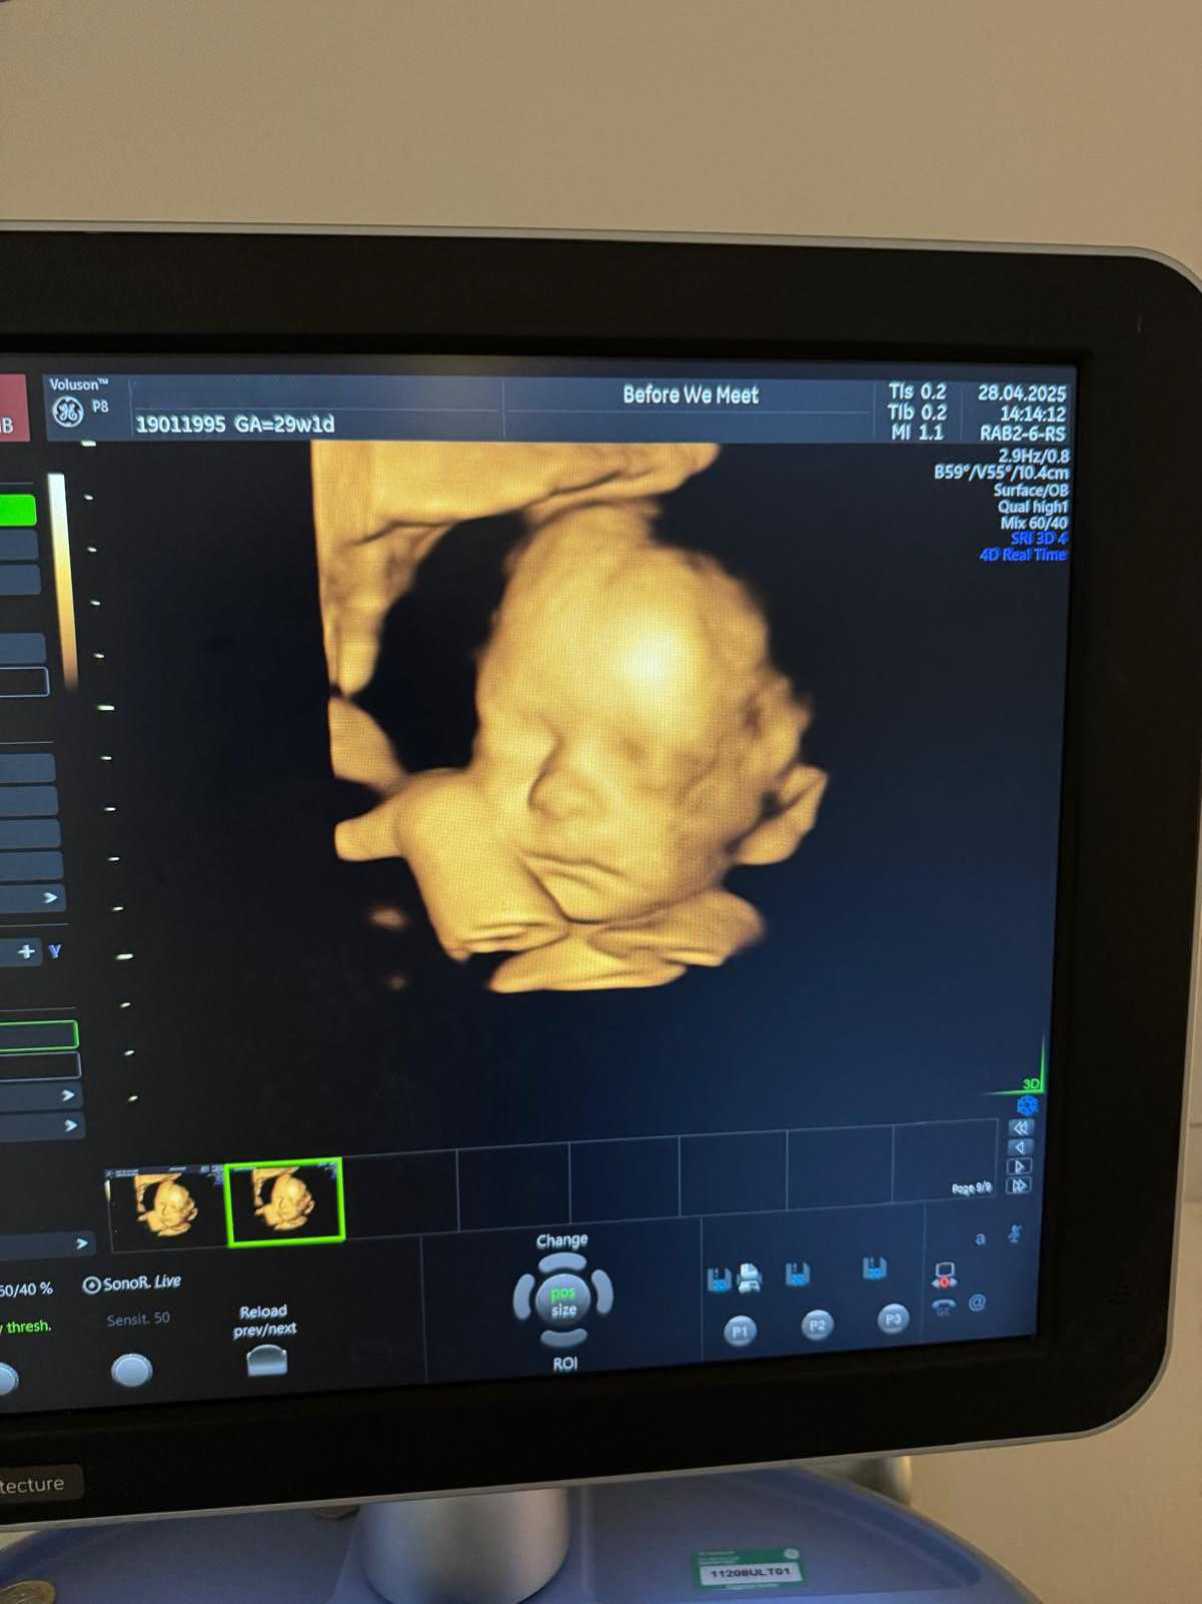

Unlike traditional 2D scans, which provide flat, black-and-white images, a 4D scan uses advanced ultrasound technology to create a moving, lifelike video of your baby in the womb. You’ll be able to see them stretch, yawn, wriggle, or even suck their thumb, beautiful little moments that feel nothing short of magical.

You can have a 4D Scan from 24 - 32 weeks of pregnancy. At this stage, your baby has developed enough facial features to be seen clearly, and there’s still enough amniotic fluid for us to capture detailed, high-quality images. If you’re unsure about timing, our team will happily advise you to make sure you get the best results possible.

Many parents tell us that their 4D scan was the moment they really felt connected to their baby. Whether it’s the first time seeing their tiny smile or catching a wave mid-kick, these scans create memories that last a lifetime.